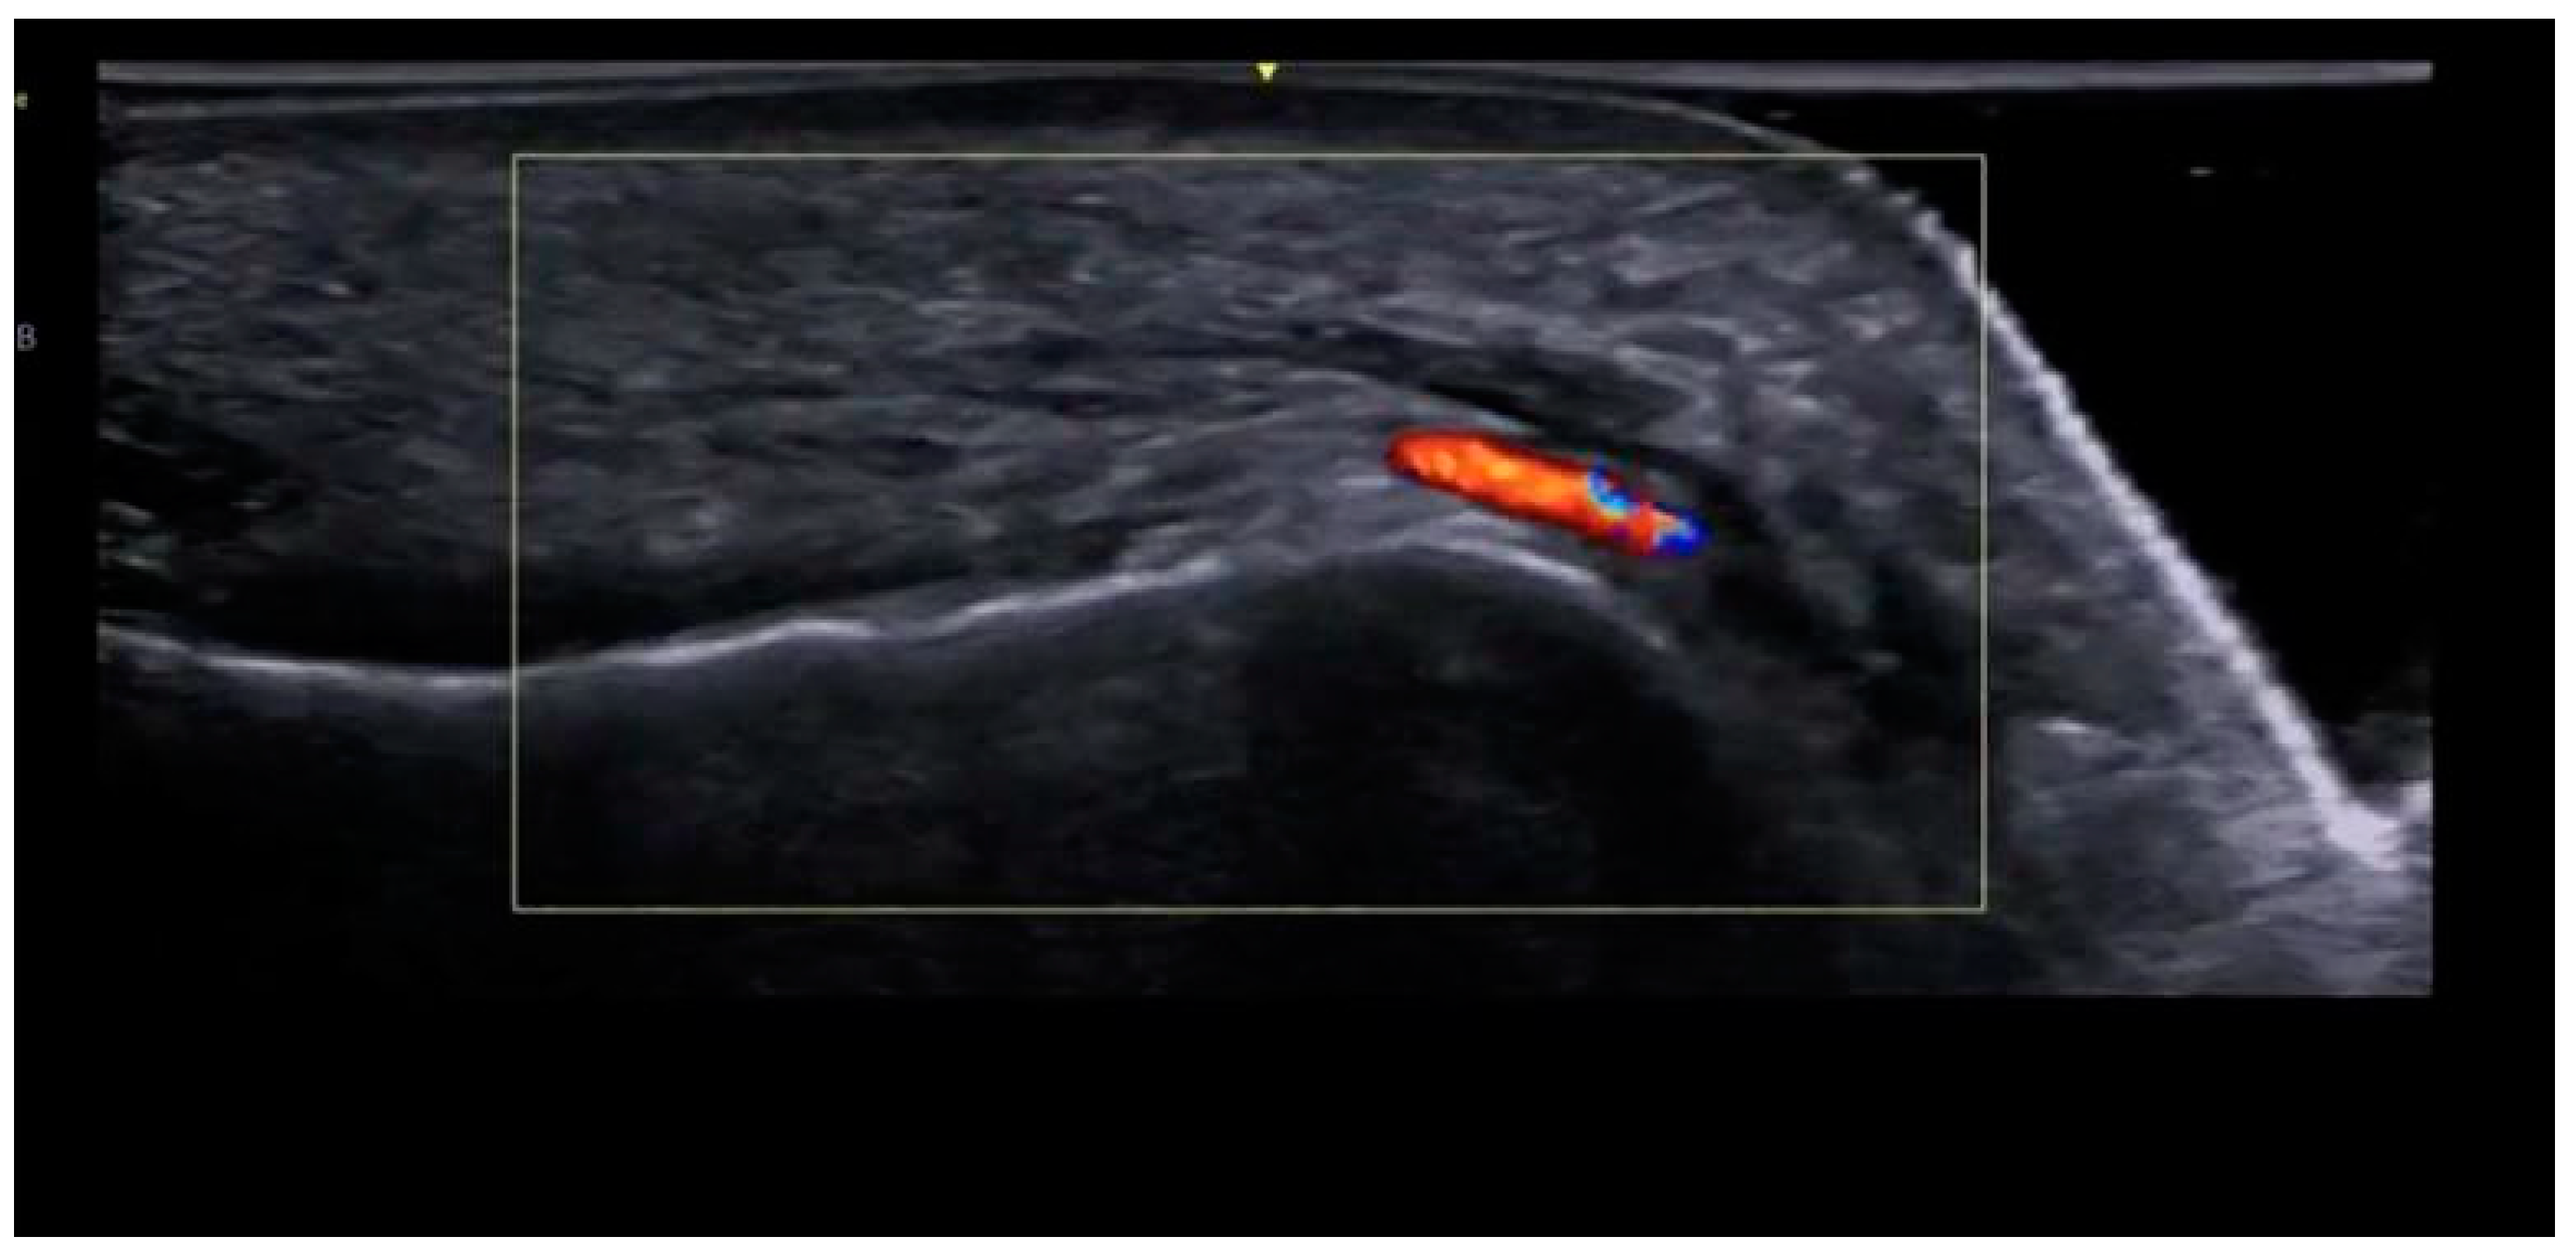

3.2. Labiomandibular Folds or Marionette Lines

Ultrasound-Guided Filling Techniques of the Marionette Line

- Subcutaneous filler placement with a blunt cannula

- Submuscular filler placement with a blunt cannula